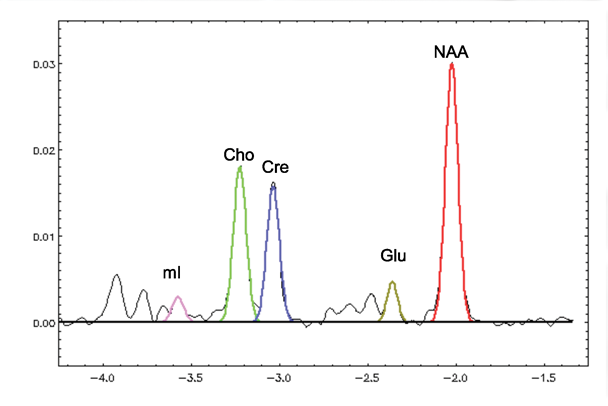

MRS reveals information about several biochemicals, or metabolites, in the brain. The largest signals arise from N-acetylaspartate (NAA), creatine and phosphocreatine (i.e., total creatine [tCr]), and choline- containing compounds (Cho). Signals from the combined resonances of glutamate (Glu) and glutamine (Gln) (i.e., Glx) are also sometimes reported, as are myo-inositiol (mI) and lactate (lac). Signals from Glu and GABA can also be detected under certain conditions.

MRI and Signals for Four Prominent Metabolites

NAA

The predominant in vivo proton signal is NAA, with contributions from other N-acetyl compounds, especially N-acetyl aspartyl glutamate. NAA is found almost exclusively in neurons (Petroff et al. 1995; Urenjak et al. 1992, 1993) and, thus, is considered a measure of neuronal integrity. Postmortem (Cooper 1972; Koller et al. 1984; Nadler and Cooper 1972) and MRS (Kwo-On-Yuen et al. 1994; Petroff et al. 1995) studies have shown NAA levels to be higher in gray than in white matter in healthy study participants, as have in vivo studies (Doyle et al. 1995; Lim and Spielman 1997; Lim et al. 1998; Moyher et al. 1995; Narayana et al. 1989; Pouwels and Frahm 1998; Schuff et al. 1999; Wang et al. 1998).

tCr

The tCr signal, generated by creatine and phosphocreatine, is influenced by the state of high-energy phosphate metabolism (Tedeschi et al. 1995). In spectroscopy studies, it often is used as a reference for other peaks based on the incorrect assumption that its concentration is relatively constant (cf. Zahr et al. 2008, 2009, 2014b).

Cho

The in vivo MRS-visible Cho peak is generated primarily by water-soluble choline-containing compounds (free choline, phosphocholine, and glycerophosphocholine) (Barker et al. 1994) and is associated with cell-membrane synthesis and turnover. The Cho resonance also provides an index of cellular density in brain tumors (Gupta et al. 1999) and may be a marker of increases in glial density with age and disease. MRS-measured Cho concentration is higher in white than gray matter (Pfefferbaum et al. 1999) and increases with normal aging (Chang et al. 1996; Kreis et al. 1993; Moats et al. 1994; Pfefferbaum et al. 1999; Soher et al. 1996).

mI

Myo-inositiol is present in glial but not neuronal cell cultures (Brand et al. 1993; Petroff et al. 1995) and plays a role in maintaining cell volume (Ernst et al. 1997; Lien et al. 1990). The concentration of mI is higher in gray than in white matter (Michaelis et al. 1993; Pouwels and Frahm 1998).

Figure 7 shows a graph of MR spectra from the thalamus of a 55-year-old nonalcoholic woman. The major metabolites are color coded.